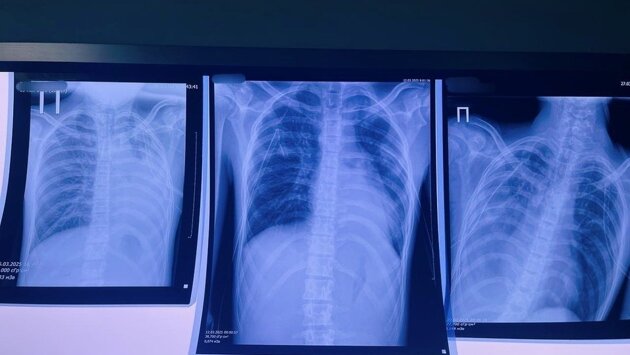

© Первоисточник

В Кирове 16-летний подросток несколько лет курил вейп. В результате в его легких образовались буллы (пузыри) в легких, которые внезапно разорвались, вызвав двусторонний пневмоторакс. Это потребовало экстренного вмешательства и перевода пациента в Федеральную клинику, где за жизнь ребенка продолжают бороться. Это не единичный случай.

Среди заболеваний появилось новое название «EVALI» – тяжелое поражение легких из-за токсичных веществ в жидкостях для вейпа, оно приводит буллезной болезни – образованию «пузырей» в легких, которые могут разорваться в любой момент. Особую опасность представляет ацетат витамина Е, при нагревании он превращается в клейкую массу, оседающую в легких. Случай в нашей клинике, произошедший с 16-летним подростком, – это тревожный сигнал. Когда мода оборачивается больничной койкой, стоит задуматься: нужно ли это «безопасное развлечение»? – задается вопросом заведующий хирургическим отделением детской областной больницы Виталий Лапшин.